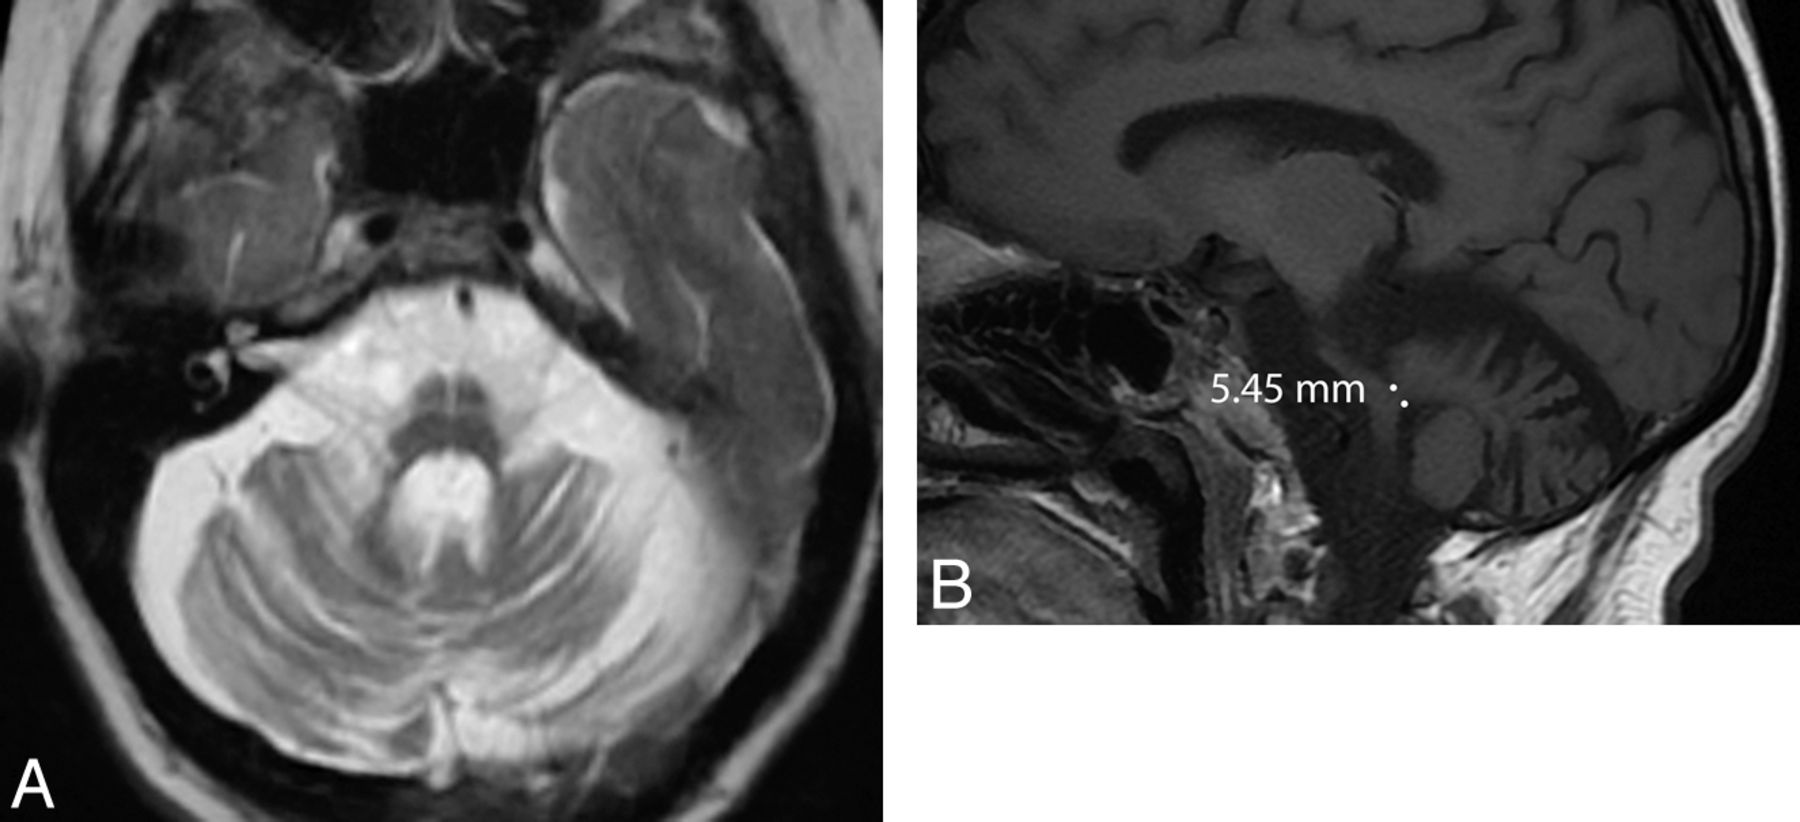

Structural MR imaging findings overlap in all MSA subtypes, independent of clinical presentation, though trends can be seen. In MSA-P, the putamen may demonstrate a rim of increased signal on T2-weighted sequences due to gliosis (Fig 1).5 In MSA with predominant cerebellar ataxia, pontocerebellar degeneration may result in visually apparent cerebellar and pontine atrophy, which, along with MSA-P to a lesser extent, is associated with increased signal on T2-weighted sequences in the middle cerebellar peduncles, cerebellum, and the pontine transverse fibers and raphe (“hot cross bun” sign) (Fig 2).

Axial T2-weighted MR imaging sequence at 1.5T in a patient with MSA-P (A) demonstrating hyperintense putaminal rims. The sign is 96% specific in differentiating patients with MSA from those with idiopathic Parkinson disease; however, it is only 56% sensitive according to 1 study.6 The corresponding coronal T1-weighted MR imaging sequence (B) shows that the putaminal rims are hypointense. The putaminal rim sign is nonspecific in the wider population—for example, it can be seen in Wilson disease or some spinocerebellar ataxia subtypes. It is also a normal finding at 3T.

Axial T2-weighted MR imaging sequence in a patient with MSA with predominant cerebellar ataxia (A) demonstrating the “hot-cross bun” sign, which results from selective loss of myelinated pontine transverse fibers and raphe neurons. One study showed that the sign is 100% specific in differentiating patients with MSA from those with idiopathic Parkinson disease; however, it is only 50% sensitive.6 Marked pontine and cerebellar atrophy is also demonstrated. This olivopontocerebellar volume loss is shown on the sagittal T1-weighted sequences (B), where a middle cerebellar peduncle width <8 mm is demonstrated. All these signs are nonspecific in the wider population—for example, they can be seen in some spinocerebellar ataxia subtypes.

Atrophy is most evident in patients with well-established disease. If one uses a cutoff value of 8 mm, the middle cerebellar peduncle width allows differentiation of patients with MSA compared with controls or those with idiopathic Parkinson disease with 100% positive predictive value (Fig 2).6 Volumetry and voxel-based morphometry group studies show striatal and cerebellar volume loss in patients with MSA-P compared with those with idiopathic Parkinson disease and controls.7⇓–9 Voxel-based morphometry also demonstrates selective cortical atrophy in MSA-P, affecting the motor cortical targets of basal ganglia output pathways such as the primary sensorimotor and lateral premotor cortices and the prefrontal and insular cortices.8